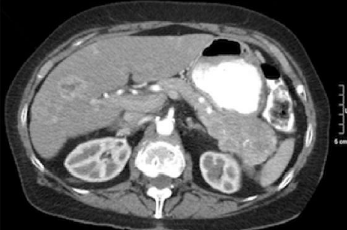

Una mujer de 58 años tiene dolor abdominal durante el último año. A la palpación se observa hipersensibilidad en el tercio medio epigástrico. Las pruebas de laboratorio muestran una concentración de lipasa sérica normal. La figura corresponde a su TC abdominal. Se extirpa la lesión y el estudio histológico revela células con atipia citológica y arquitectural pero que no infiltran el parénquima pancreático adyacente. ¿Cuál es el diagnóstico más probable?

C. Neoplasia mucinosa quística La TC muestra una masa quística multilocular delimitada. Los tumores mucinosos pancreáticos pueden ser completamente benignos, intermedios (borderline) o malignos. La presencia de atipia citológica y arquitectural (displasia de bajo grado) es indicativa de que la lesión no es totalmente benigna, pero cuando no existen rasgos claramente malignos, como infiltración o metástasis, la lesión se debe incluir dentro de la categoría borderline. Esta terminología «indefinida» resulta frustrante para los profesionales sanitarios y los pacientes, pero con frecuencia no existen respuestas sencillas a la hora de abordar estas neoplasias. Sin embargo, con el tiempo puede aparecer un adenocarcinoma sobre una neoplasia mucinosa quística. Los adenocarcinomas de páncreas son neoplasias sólidas más invasivas, de mal pronóstico en general. Los quistes de la PQRAD son benignos y aparecen dispersos por todo el páncreas sin condicionar un efecto de masa; la TC de este caso no muestra quistes renales. La fibrosis quística puede producir una pancreatitis crónica, pero no una neoplasia pancreática. Los tumores de las células de los islotes son masas sólidas, en general, bastante pequeñas cuando son benignas y en ocasiones se asocian a producción hormonal. Un seudoquiste es una estructura inflamatoria originada sobre una pancreatitis con necrosis extensa y no se trata de una neoplasia.